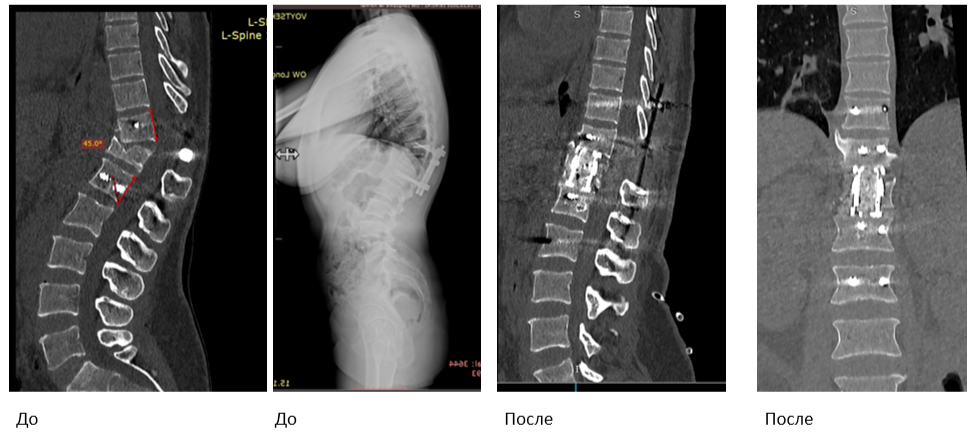

Ей выполнили ляминэктомию 12 грудного позвонка и короткосегментарную транспедикулярную фиксацию позвоночника. К сожалению, со временем металлоконструкция показала свою несостоятельность и сломалась, что привело к неминуемой потере коррекции и появлению грубой деформации позвоночника.

Именно с этим мы столкнулись у нашей пациентки. Через несколько лет в результате недостаточной стабильности фиксации произошел усталостный перелом металлоконструкции в результате циклических нагрузок в процессе жизнедеятельности пациентки. Сформировался грубый комбинированный (посттравматический+ постляминэктомический) грудопоясничный кифоз (50 градусов), сопровождающийся выраженными болями в спине. Почему так болит? Потому что деформация позвоночника приводит к дисбалансу туловища, включению компенсаторных механизмов и колоссальному перенапряжению мышц, обеспечивающих вертикальное положение тела в пространстве. Это молодая женщина трудоспособного возраста, состояние которой не позволяло вести полноценную жизнь, и помочь ей могла только хирургическая реконструкция позвоночника. Мы приняли решение о проведении трехэтапной операции в одну хирургическую сессию», — объясняет к.м.н., спинальный хирург, заместитель директора по лечебной работе Алексей Ластевский.

Первый этап выполнялся из заднего доступа — когда пациент лежит на животе, а разрез выполняется со стороны спины. Несостоятельная металлоконструкция была удалена, выполнена хирургическая мобилизация задних структур на уровне Th11-Th12. Этот этап операции называется остеотомия позвоночника (дословно: «пересечение позвоночника») — чтобы обеспечить в момент второго этапа возможность исправить деформацию. Первую операцию провёл спинальный хирург Кирилл Аникин.

Второй и третий этап проходил под руководством Алексея Ластевского. Как объясняет эксперт, далее пациент переворачивается на спину и укладывается на операционный стол определенным образом. Передняя операция на позвоночнике выполняется через грудную клетку, т.е. применяется хирургический доступ через плевральную полость справа (торакотомия).

При проведении этого этапа при помощи специальных инструментов хирург удаляет разрушенное и неопорное тело позвонка, добивается получения необходимой подвижности на этом уровне. Далее проводится реконструкция передней колонны позвоночника с помощью современной лифтовой системы — раздвижного телескопического кейджа отечественного производства, который устанавливается вместо Th12 позвонка, тем самым восстанавливается опорная функция позвоночника.

Завершающий этап операции вновь проводится через задний доступ. В этот момент проводится окончательная задняя стабилизация, винты соединяются между собой специальными штангами и фиксируются гайками. В итоге получается очень жесткая циркулярная фиксация (360 градусов). Все три этапа проходили за один день и в общем заняли порядка 8 часов — такие операции возможны благодаря слаженной работе всей хирургической бригады. В команде также работали врач-анестезиолог-реаниматолог Иван Стаценко, операционная медсестра Нина Хромова и медсестра-анестезист Татьяна Массон

Задач у такой хирургии несколько: помимо чисто косметического эффекта, восстановление сагиттального профиля позвоночника позволяет выключить механизмы компенсации (поясничный гиперлордоз и грудной гипокифоз). Гармонизируя сагиттальный профиль позвоночника, специалисты приводят в соответствие параметры баланса: поясничный лордоз, грудной кифоз и разворот таза. Цель была достигнута — врачам удалось вернуть гармонию изгибов позвоночника. Колоссальное перенапряжение мышц уйдёт, а вместе с ним пациентку покинут и сильные мучительные боли.